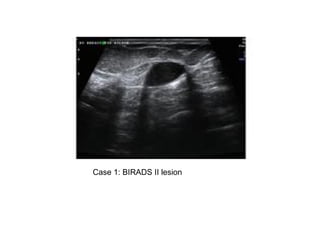

Case 1: BIRADS II lesion

Case 1: BIRADSII lesion